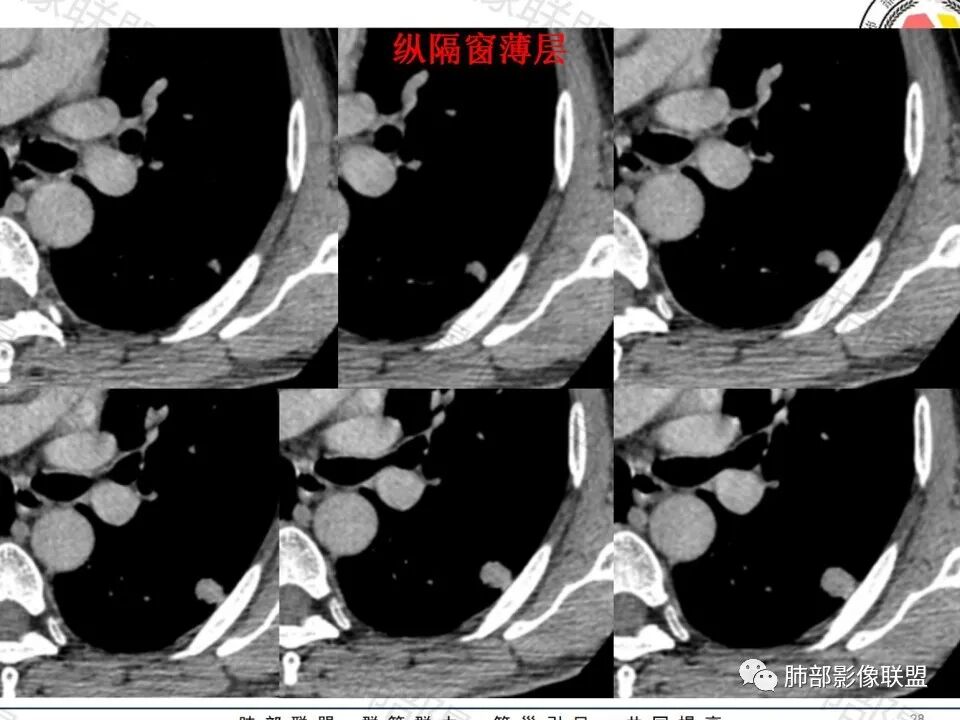

病史:男,60岁,体检左下肺结节,肿标阴性;

影像:轻微肺气肿,可能抽烟;旁边有个卫星灶4-5个,厚层无血管弯,薄层叶间裂轻度增厚,有囊腔,内侧有一个微血管,弯,另有两个微血管直,膨隆,增强血管不弯,糊墙,好像边界有些模糊,17-47-47,冠位轻度叶间裂弯。

诊断:警惕良性,隐球菌感染?

鉴别:腺癌,无磨玻璃,模糊?糊墙;纵膈窗太光滑,胸膜面广;不膨隆。支持点,薄层毛刺,强化。

类圆形,边缘稍平直,周围晕中细微毛刺,密度均匀,均匀强化,血管走形自然,稍牵拉扭曲,支气管在近端堵塞

这枚结节的纵隔窗在没有调节窗位的情况下,已经很密实了,说明这个结节里面是软组织的成分,这与普通炎性结节(隐球菌等)的密度还是有区别的,很多年前就有人提出,纵隔窗显示越大,恶性可能越大;

结节周围有磨玻璃影,边界似清不清的,但是总体不如炎性晕征那么模糊;

增强的程度很难讲,但是不均匀强化是可以确定的;

有收缩力,但是很轻,按照常理,实性结节因为有占位效应,不太会有收缩力,但是叶间胸膜有凹陷。所以讲,这个结节还是开了放心。